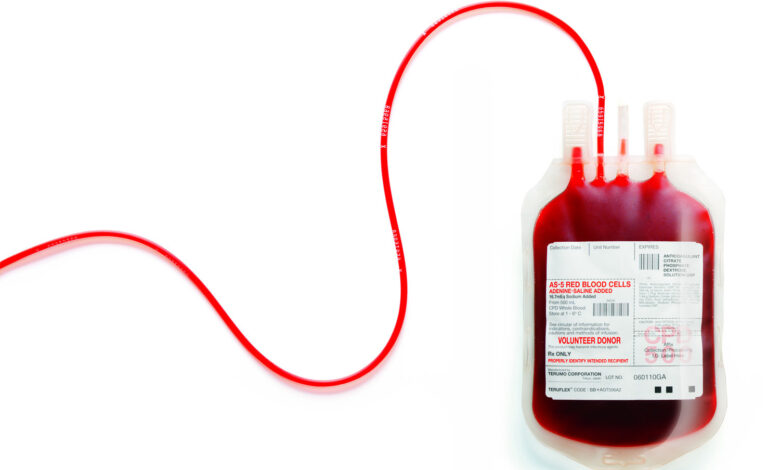

روز جهانی اهدای خون

روز (۱۴ ژوئن) هر سال به نام روز جهانی اهدای خون (روز جهانی تقدیر از اهدا کنندگان خون) انتخاب شدهاست. در این روز از همت والا و فعالیت انسان دوستانه تمام کسانی که در زمینه اهدا و انتقال خون و نجات جان انسانها تلاش میکنند، قدردانی میشود.سازمان بهداشت جهانی، جامعه بین المللی انتقال خون، انجمن بین المللی صلیب سرخ و هلال احمر و اتحادیه بین المللی سازمان های اهداکنندگان خون به اتفاق از سال 2004 میلادی ( 1383) ،14 ژوئن را روز جهانی اهداکننده خون نامگذاری نمودند و از همه کشورها خواستند در این روز برای بزرگداشت اهداکنندگان برنامه ریزی نمایند. انتخاب این روز به مناسبت تولد پروفسور لنداشتاینر کاشف گروه های خون و برنده جایزه نوبل بود که طب انتقال خون پس از این کشف بزرگ پیشرفت زیادی کرد.

تولد کارل لانداشتاینر

کارل لانداشتاینر متولد 14ژوئن1868 بود . او پزشک و ایمونولوژیست اتریشی و برنده جایزه نوبل فیزیولوژی- پزشکی 1930 برای توسعه سیستم مدرن طبقه بندی گروه های خونیاست که در 26 ژوئن 1943 درگذشت.